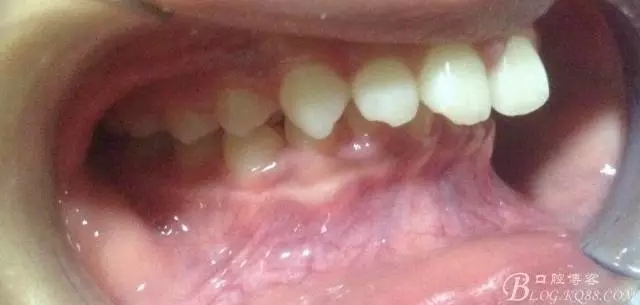

看看口內(nèi)照吧!真象“大暴牙”v假象“大暴牙”

三度深覆合,三度深覆蓋,尖牙,磨牙均二類關系!